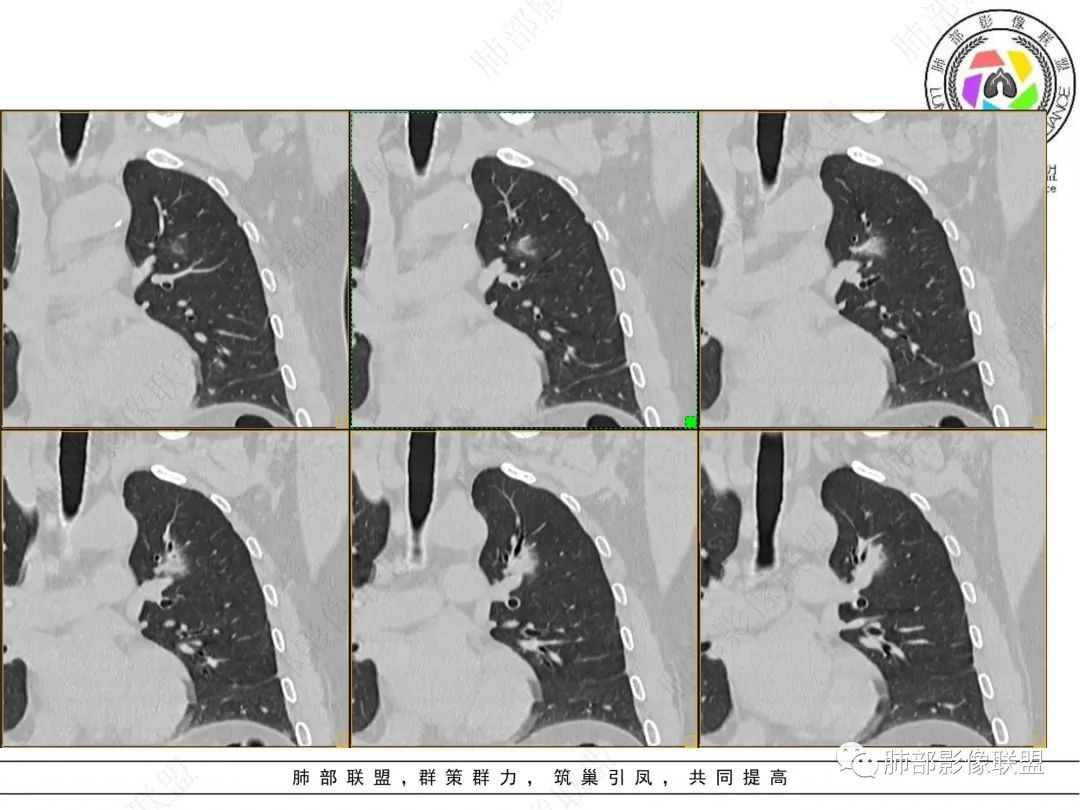

男性,肺结节3年,发现逐渐增大,影像表现,左肺舌段结节,边缘可见磨玻璃密度影,内部走形下舌段支气管变窄,增强呈持续强化,首先考虑肺腺癌,鉴别炎性肉芽肿,真菌/隐球菌。

中老年男性,发现结节,影像表现,左肺上叶结节,实性部分有膨胀性生长,边缘可见磨玻璃影,似清晰似不清晰,病灶与支气管关系密切,部分支气管似狭窄及僵硬,增强病灶强化明显,考虑腺癌(粘液性腺癌)鉴别炎性肉芽肿。

左肺上叶尖段支气管旁结节伴磨玻璃影,磨玻璃影边缘模糊,支气管走形正常,病变无明显分叶及毛刺,收缩不明显,增强呈延迟高强化。先考虑炎性肉芽肿。肿瘤待排。

左肺上叶支气管旁结节伴磨玻璃影,磨玻璃边缘略模糊,沿支气管走行,明显不均匀延迟强化,3年逐渐增大,考虑腺癌,鉴别淋巴增殖病变,炎性肉芽肿

中年男性,体检发现左上肺结节,影像:左上肺欠规则结节+磨玻璃(边界欠清),沿支气管爬行生长,支气管无受累,增强后明显渐进性强化,3年随访增大,考虑低度恶性肿瘤,如淋巴增殖性病变,如淋巴瘤样肉芽肿可能。

左肺上叶前段实性结节,沿支气管血管束生长,整体形态近三角形,边缘模糊,累及前段气管主支管壁增厚,管腔通畅,前后复查不足两年病灶倍增明显,肿瘤指标阴性,支持炎性肉芽肿,2019年10月2日首诊图,主体结节外周似有小卫星灶分布,需薄层确认,支气管镜肺泡灌洗检查。

361度:

2、病灶以实性密度为主,前、外侧蔓延,GGO部分边界清楚,部分欠清

支气管未见受明显侵犯,未见阻塞,壁增厚,狭窄或扩张。

软组织+重建;病灶实性部分不是类圆形,密度相对均匀柔和。

肺门区病灶与支气管关系不密切,强化显著、磨玻璃晕等等容易想到的是肺腺癌。而不首先考虑与支气管密切相关恶性肿瘤,如鳞癌、类癌、粘液表皮样癌等等。